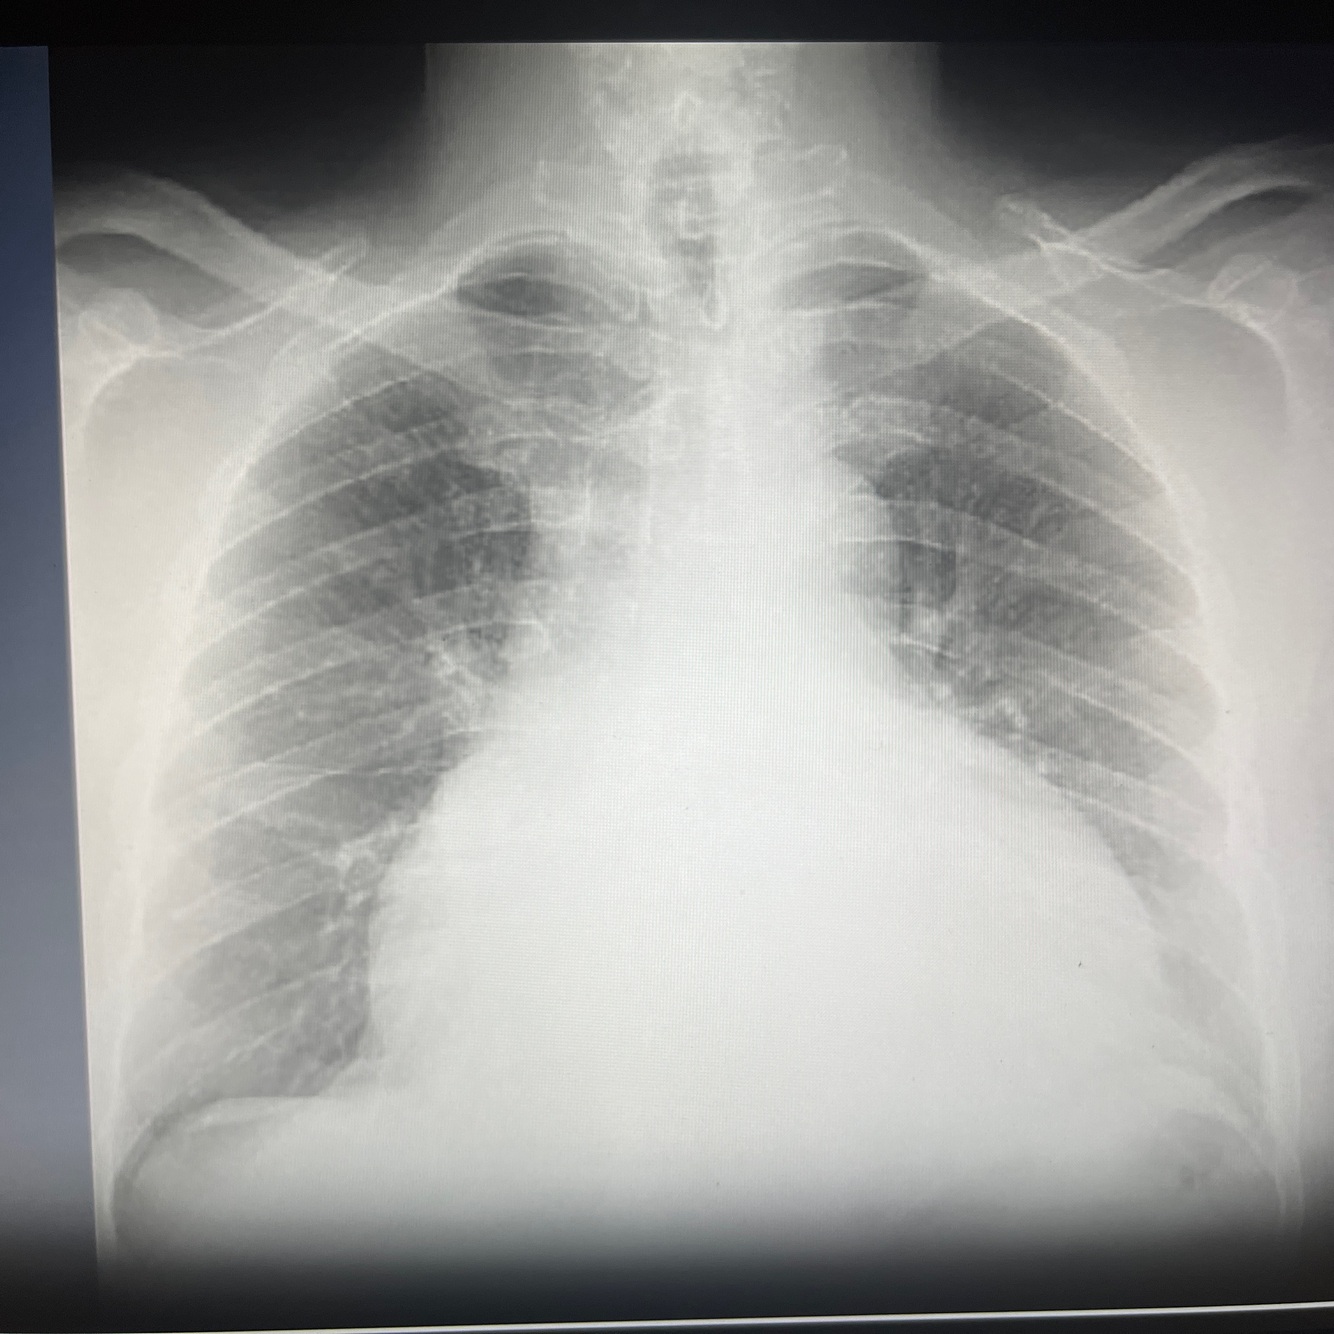

Opacification over lower lobes

Pneumonia with some form of collapse